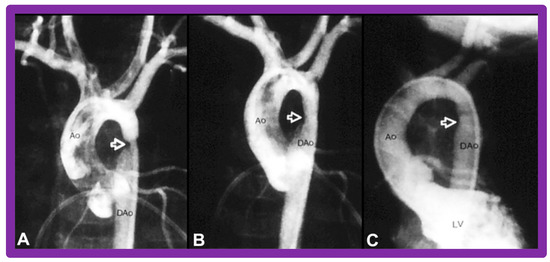

6.3. Aortic Coarctation–Native

6.4. Aortic Coarctation, Postsurgical